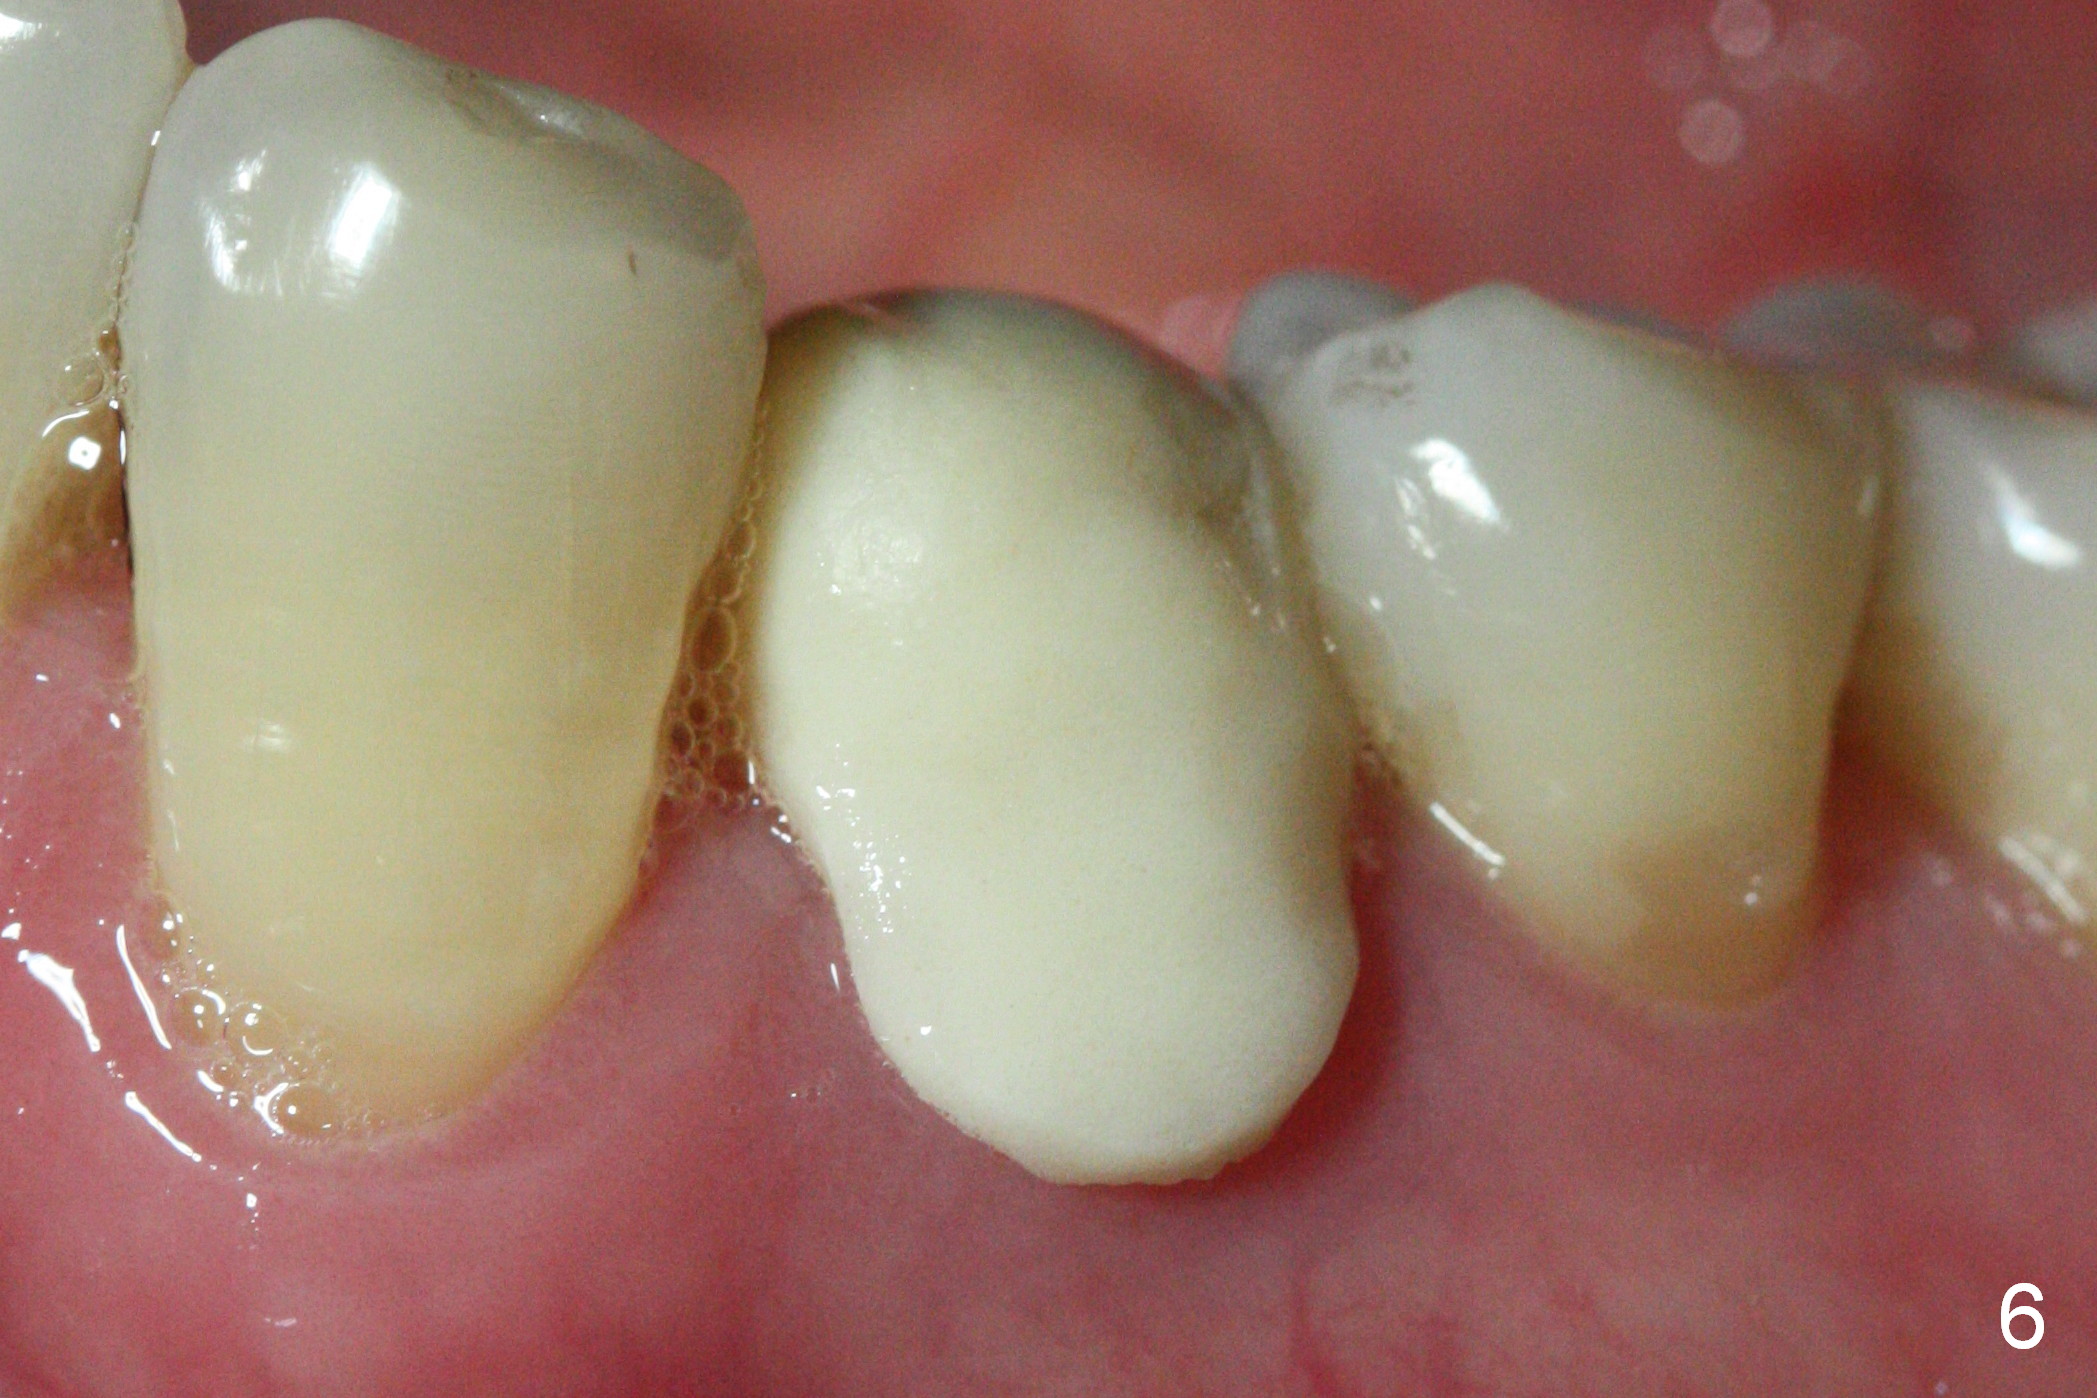

The patient returns for provisional revision 2 weeks postop (Fig.6). The bone graft remains in place (Fig.7). The buccal margin of the provisional is reduced (Fig.8).